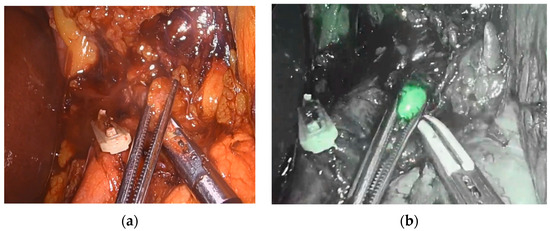

2.5. ESOMAP Protocol